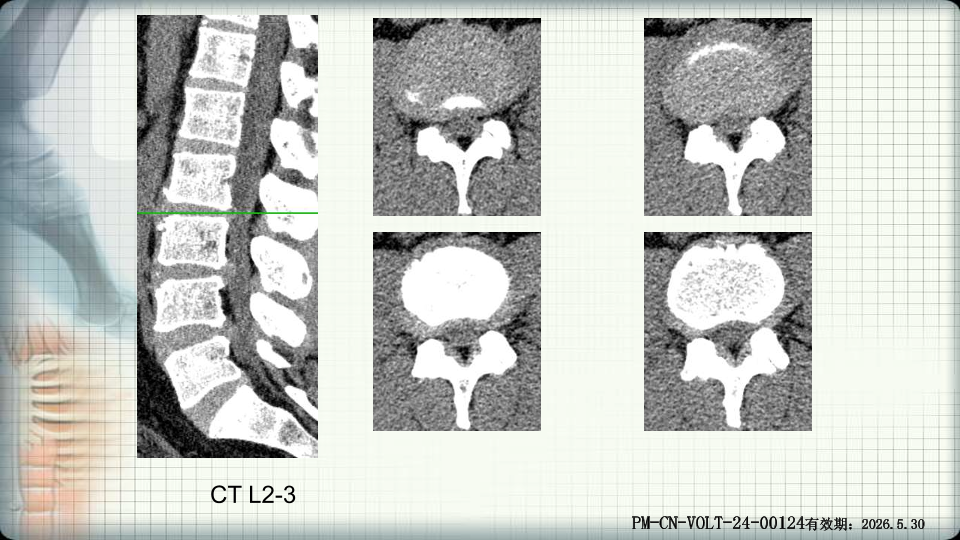

管狭窄症非手术治疗-谢学虎